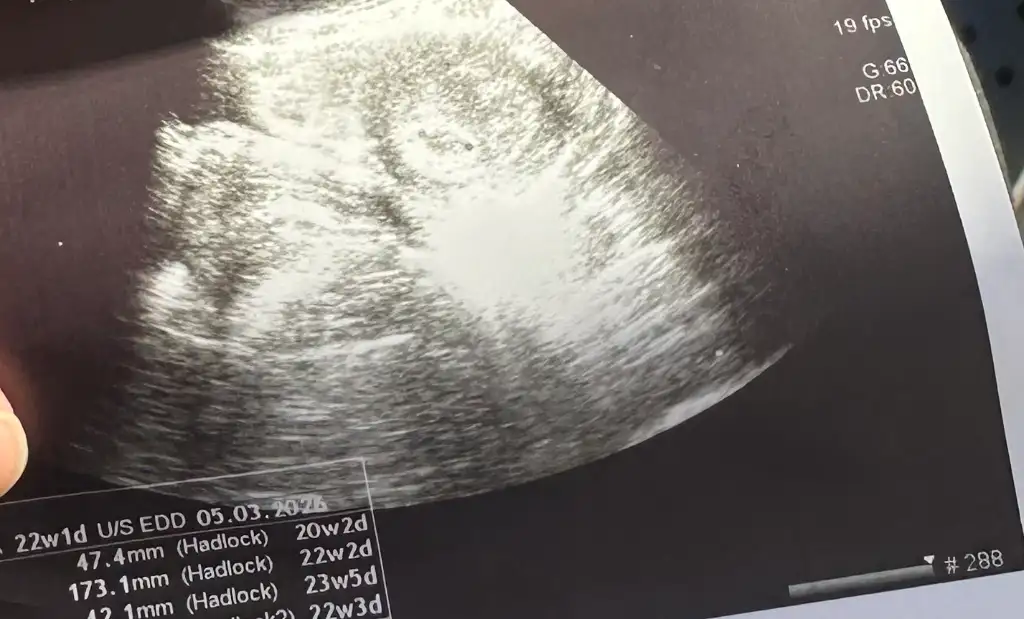

Kızlar keseyi görenler ultrason fotoğrafı varsa bana gösterebilirmi şimdi geldim ben doktordan ama anlayamadım ya elinde görüntğ olan varmı

Doktor görüntü vermedi keseyi gördü fakat kese baya yayvan bi şekilde duruyor kan istedi ben ikinci kan vermemiştim ikiz gebelikten şüphelendi biraz moralim bozuk